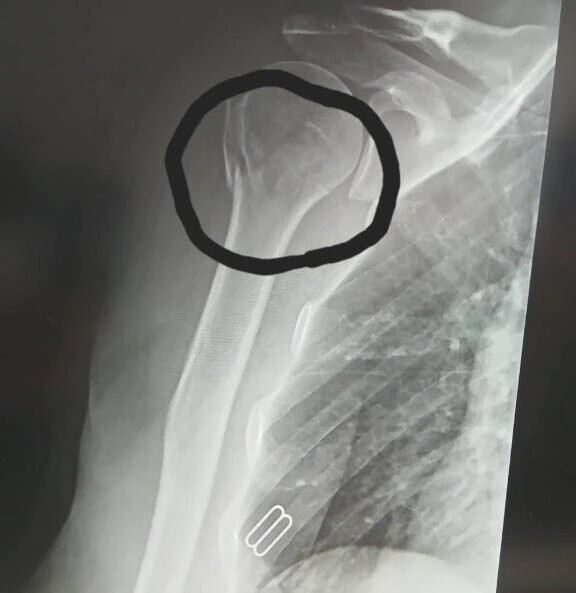

階段から落ちて

腕と足首

骨折しちゃったので🥺💦

復帰まで

3〜6ヶ月らしい‥(TT)